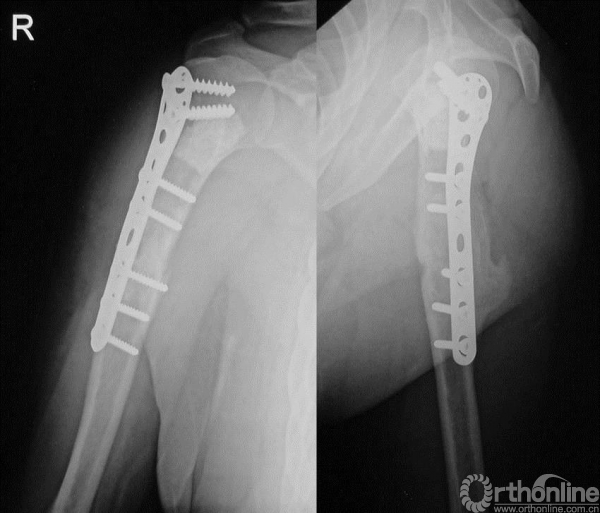

手术

术前未行化疗,手术行“左肱骨上段瘤段截除、异体骨置换、钢板内固定术”。肱骨上端肿瘤切除后骨缺损的重建有多种方法,肱骨上段骨缺损重建因肩关节结构的特殊性,依肿瘤学的要求行肿瘤外科学的广泛切除,导致肩袖软组织缺损,术后肩关节稳定性差,常常出现肱骨头向前上方脱位。肱骨异体骨大段移植,可以将自体软组织、残留的关节囊组织缝合至异体骨,术后制动软组织粘连于异体骨,有利于肩关节稳定和部分肩外展功能的恢复。

图13-11 病例一第二次术后X线平片正位

图13-14 病例一第二次术后4个月X线平片正侧位(第一次术后10个月)